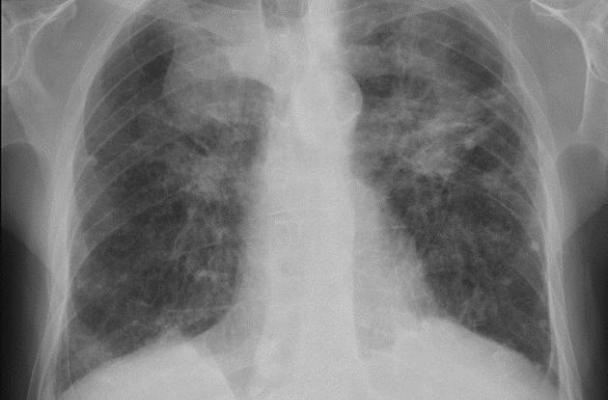

Black Lung is a disease caused by breathing coal mine dust. It is incurable and often gets worse over time. Treatment is limited to relieving symptoms and preventing complications. Nearly 76,000 miners have died from black lung disease since 1969 – the year coal mine dust regulations were put in place.

Miners still get the disease, and the most severe form, progressive massive fibrosis, is on the rise in Appalachia.